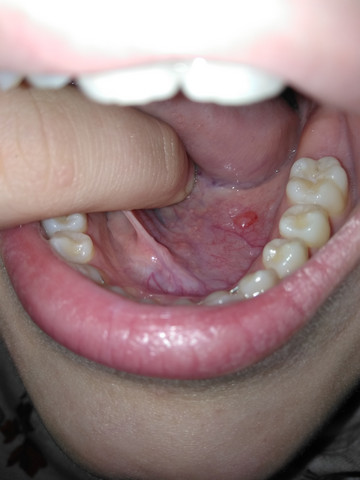

Blase an der zungenspitze. Selten kann auch die Zungenspitze betroffen sein. Schmerzhafte Entzündungen hingegen deuten auf Aphthen hin und diese entstehen an der Zungenspitze und machen sich bis zum Zungenrand breit. Bei einer Zufuhr von Nahrung oder Flüssigkeit werden die Schmerzen meist noch unerträglicher.

Doch es können sich auch Bläschen auf der Zunge zeigen die einige Zeit bestehen bleiben und meistens schmerzhaft sind. Blase auf der Zunge - die Ursachen Haben Sie etwas zu heiß gegessen können Sie sich die Zunge verbrennen. Die Bläschen werden manchmal auch als Lügen-Bläschen bezeichnet.

Blasen auf der Zunge sind sehr kleine runde bis ovale Bläschen die mit Flüssigkeit gefüllt sind. Der Schmerzcharakter kann dabei von einem Pulsieren bis zu einem Brennen variieren. Der brennende Schmerz kann dabei auf einen bestimmten Bereich der Zunge beschränkt oder diffus über der ganzen Zunge zu spüren sein.

Dann leidest du vielleicht an einer verbreiteten Krankheit namens transiente Zungenpapillitis. Der medizinische Fachbegriff für Bläschen auf der Zunge ist Vesikel. Erste Symptome eines Zungenkrebses.

Ein Brennen an der Zungenspitze bzw. Bereitet ein Tumor an der Zunge den meisten Betroffenen anfangs noch keine Beschwerden so wächst die Geschwulst mit der Zeit immer weiter heran.

Schmerzen an der Zungenspitze sind als unangenehme Empfindungen im vorderen Drittel der Zunge definiert. Der medizinische Fachbegriff für Bläschen auf der Zunge ist Vesikel. Meine Tochter 9 Monate hat seit heute eine weiße minimal gelbliche Blase an der Zungenspitze. Sie ist gut drauf kein Fieber Hände und Füße unauffällig. Neben Sprache und Geschmacksempfinden ist sie oft ein primärer Indikator für Ihre allgemeine Gesundheit. Bläschen auf der Zunge. Schmerzhafte Entzündungen hingegen deuten auf Aphthen hin und diese entstehen an der Zungenspitze und machen sich bis zum Zungenrand breit. Wer zu heißt gegessen hat der hat sich im wahrsten Sinne des Wortes die Zunge verbrannt und eine Blasenbildung entsteht. Erste Symptome eines Zungenkrebses.

Selten kann auch die Zungenspitze betroffen sein. Doch es können sich auch Bläschen auf der Zunge zeigen die einige Zeit bestehen bleiben und meistens schmerzhaft sind. Bläschen auf der Zunge. Der medizinische Fachbegriff für Bläschen auf der Zunge ist Vesikel. Die erweiterten Symptome einer vorgefallenen Blase gehören ein Vorsprung der einen Golfball-Größe Klumpen in der Öffnung der Vagina schafft Schmerzen im Beckenbereich die während des Geschlechtsverkehrs die nicht kontrolliert werden kann immer schlimmer wird beim Wasserlassen Schmerzen die in zurück stammt der untere und beginnt um mehr von den Rücken und schmerzhaften Infektionen der Blase. Ein Brennen an der Zungenspitze bzw. Die gesunde Zunge verfügt über eine blass-rosa Farbe sowie eine regelmäßig feuchte und etwas raue Oberfläche.